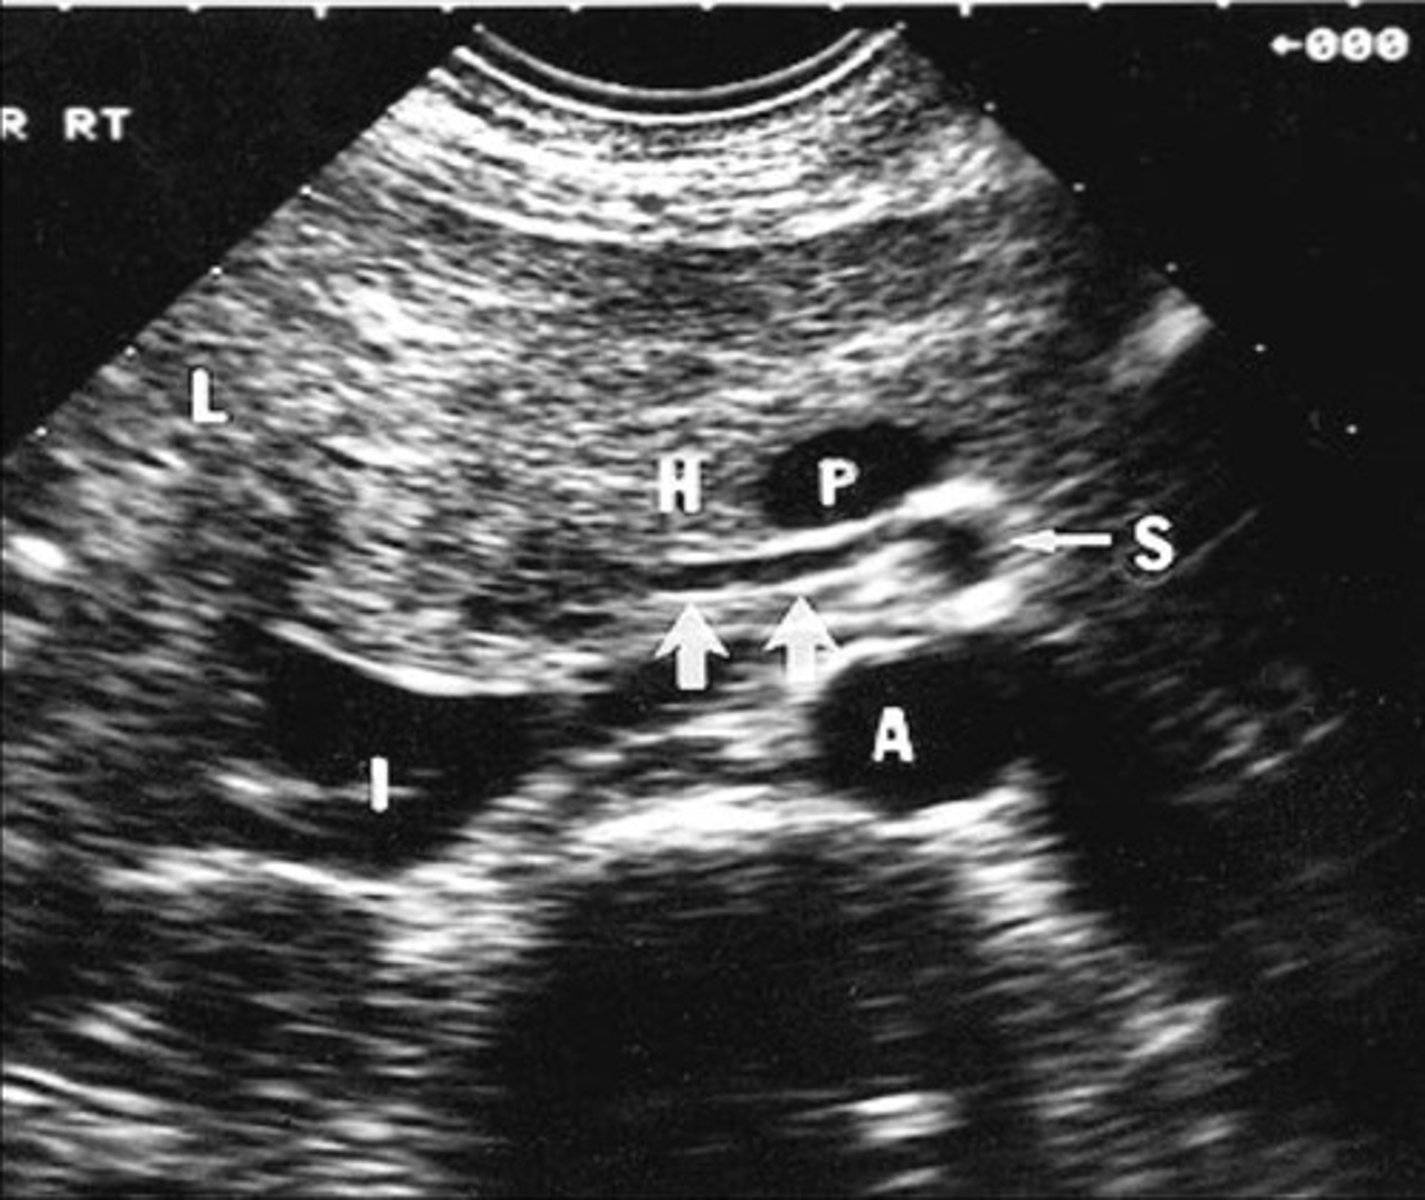

Aorta at level of celiac axis and SMA

Origin of celiac axis

Origin of SMA

Celiac Artery